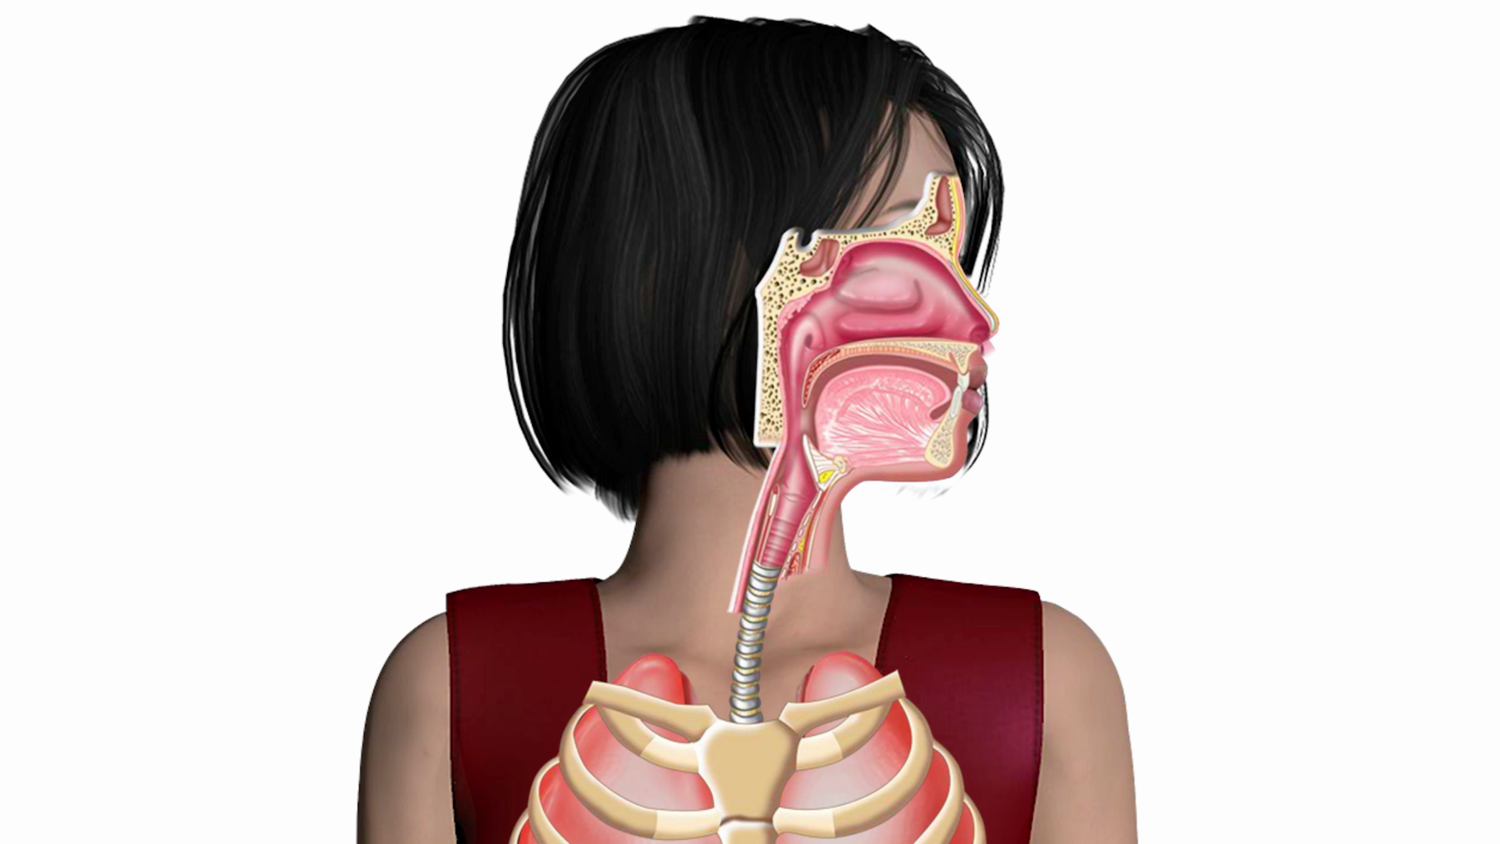

Module 2 - How the Voice Works

In this module we explore the four parts of every instrument and then talk about what those parts are in the voice.

Module 4 - Respiration

In module 4 you will learn about the larynx. We are going to focus on the big picture, introducing you to the terms you are most likely to hear in conversations with others singers, teachers, or coaches.

Module 6 - Vocal Tract

After vibrations leave the vocal folds, they travel through the vocal tract where the sound is transformed into vowels and consonants. In module 6, we dive into each of these parts, how the move, and how they alter vocal quality.